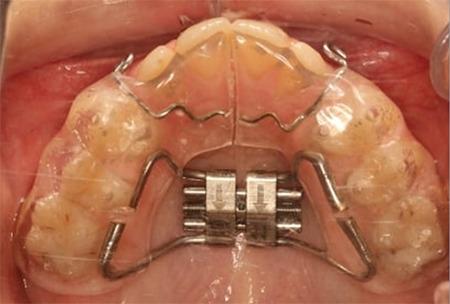

The study consisted of 79 (37 and 42 patients in the RME and Alt-RAMEC groups with FM, respectively) patients who had received FM treatment. The effects of the RME/FM (20 female, 17 male) and Alt-RAMEC/FM (14 female, 28 male) protocols were evaluated using lateral cephalometric films. The chronological ages of the RME/FM and Alt-RAMEC/FM groups were 11.58 and 11.99 years, respectively. In addition, both groups were divided into two subgroups based on the design of the expansion appliance (Spolyar or full coverage type). Differences in all parameters were analyzed using Student's t-tests.

The maxilla significantly moved forward in both the RME/FM and Alt-RAMEC/FM groups (p<0.001). No significant skeletal differences were observed between the groups. Sagittal movement of the upper incisors significantly increased, and the lower incisors significantly retruded in both groups. While similar skeletal changes were found between the Spolyar and full-coverage appliance groups, the upper incisors protruded significantly more in the full-coverage type.

RME/FM and Alt-RAMEC/FM therapies were found to be efficient for maxillary protraction and resulted in similar skeletal changes. A full-coverage expansion appliance produced a more upper incisor protrusion than a spherical-type appliance.